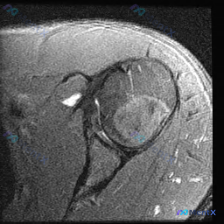

整理到一个肩部MRI的病例讨论材料。先看提供的单张冠状位T2加权图像: - 冈上肌腱:低信号条带连续性存,但信号不均、有增高,未见过层撕裂 - 肩峰下-三角肌下滑囊:可见明显T2高信号积液,提示滑囊炎症 - 盂唇区域:显示不清,无明确的撕裂、分离或移位征象 - 骨骼/关节:肱骨头、关节盂信号正常,对...

整理了一份肩关节MRI影像的病例讨论。这是一张冠状位T2加权序列图像,原问题主要想了解盂唇病理。大家先看这份影像分析,最突出的发现是什么?目前主要考虑哪些诊断?

看到一份肩关节MRI病例讨论材料,用户重点关注「盂唇病变」,但影像显示冈上肌腱全层撕裂伴显著关节积液、滑囊炎。先放MRI关键发现: 影像类型:冠状斜位T2加权像 核心表现: - 冈上肌腱附着点(大结节处)连续性中断,肌腱内部及上方高信号 - 肩峰下-三角肌下滑囊大量液体积聚(高信号) - 关节腔内显...

最近看到一份肩部MRI-T2序列冠状位影像的分析报告,用户初始问题是关于「盂唇病变」的,但报告里还提到了冈上肌腱撕裂、肩峰下撞击综合征等内容。先不放完整结论,大家只看这些信息,觉得核心诊断应该是什么? 报告里的关键描述: - 冈上肌腱在大结节附着处有明显高信号影,形态中断及回缩 - 肩峰下-三角肌下...

最近看到一张肩关节MRI影像(冠状斜位T2加权像),用户提问能否观察到盂唇病变。先放影像分析的主要发现,大家来讨论一下: 1. 解剖定位:图像展示了肩关节冠状斜位切面,主要观察盂肱关节、肱骨头上方、肩峰下间隙及冈上肌肌腱的走行和附着情况 2. 影像表现:冈上肌肌腱在肱骨大结节附着区域连续性中断,可见...